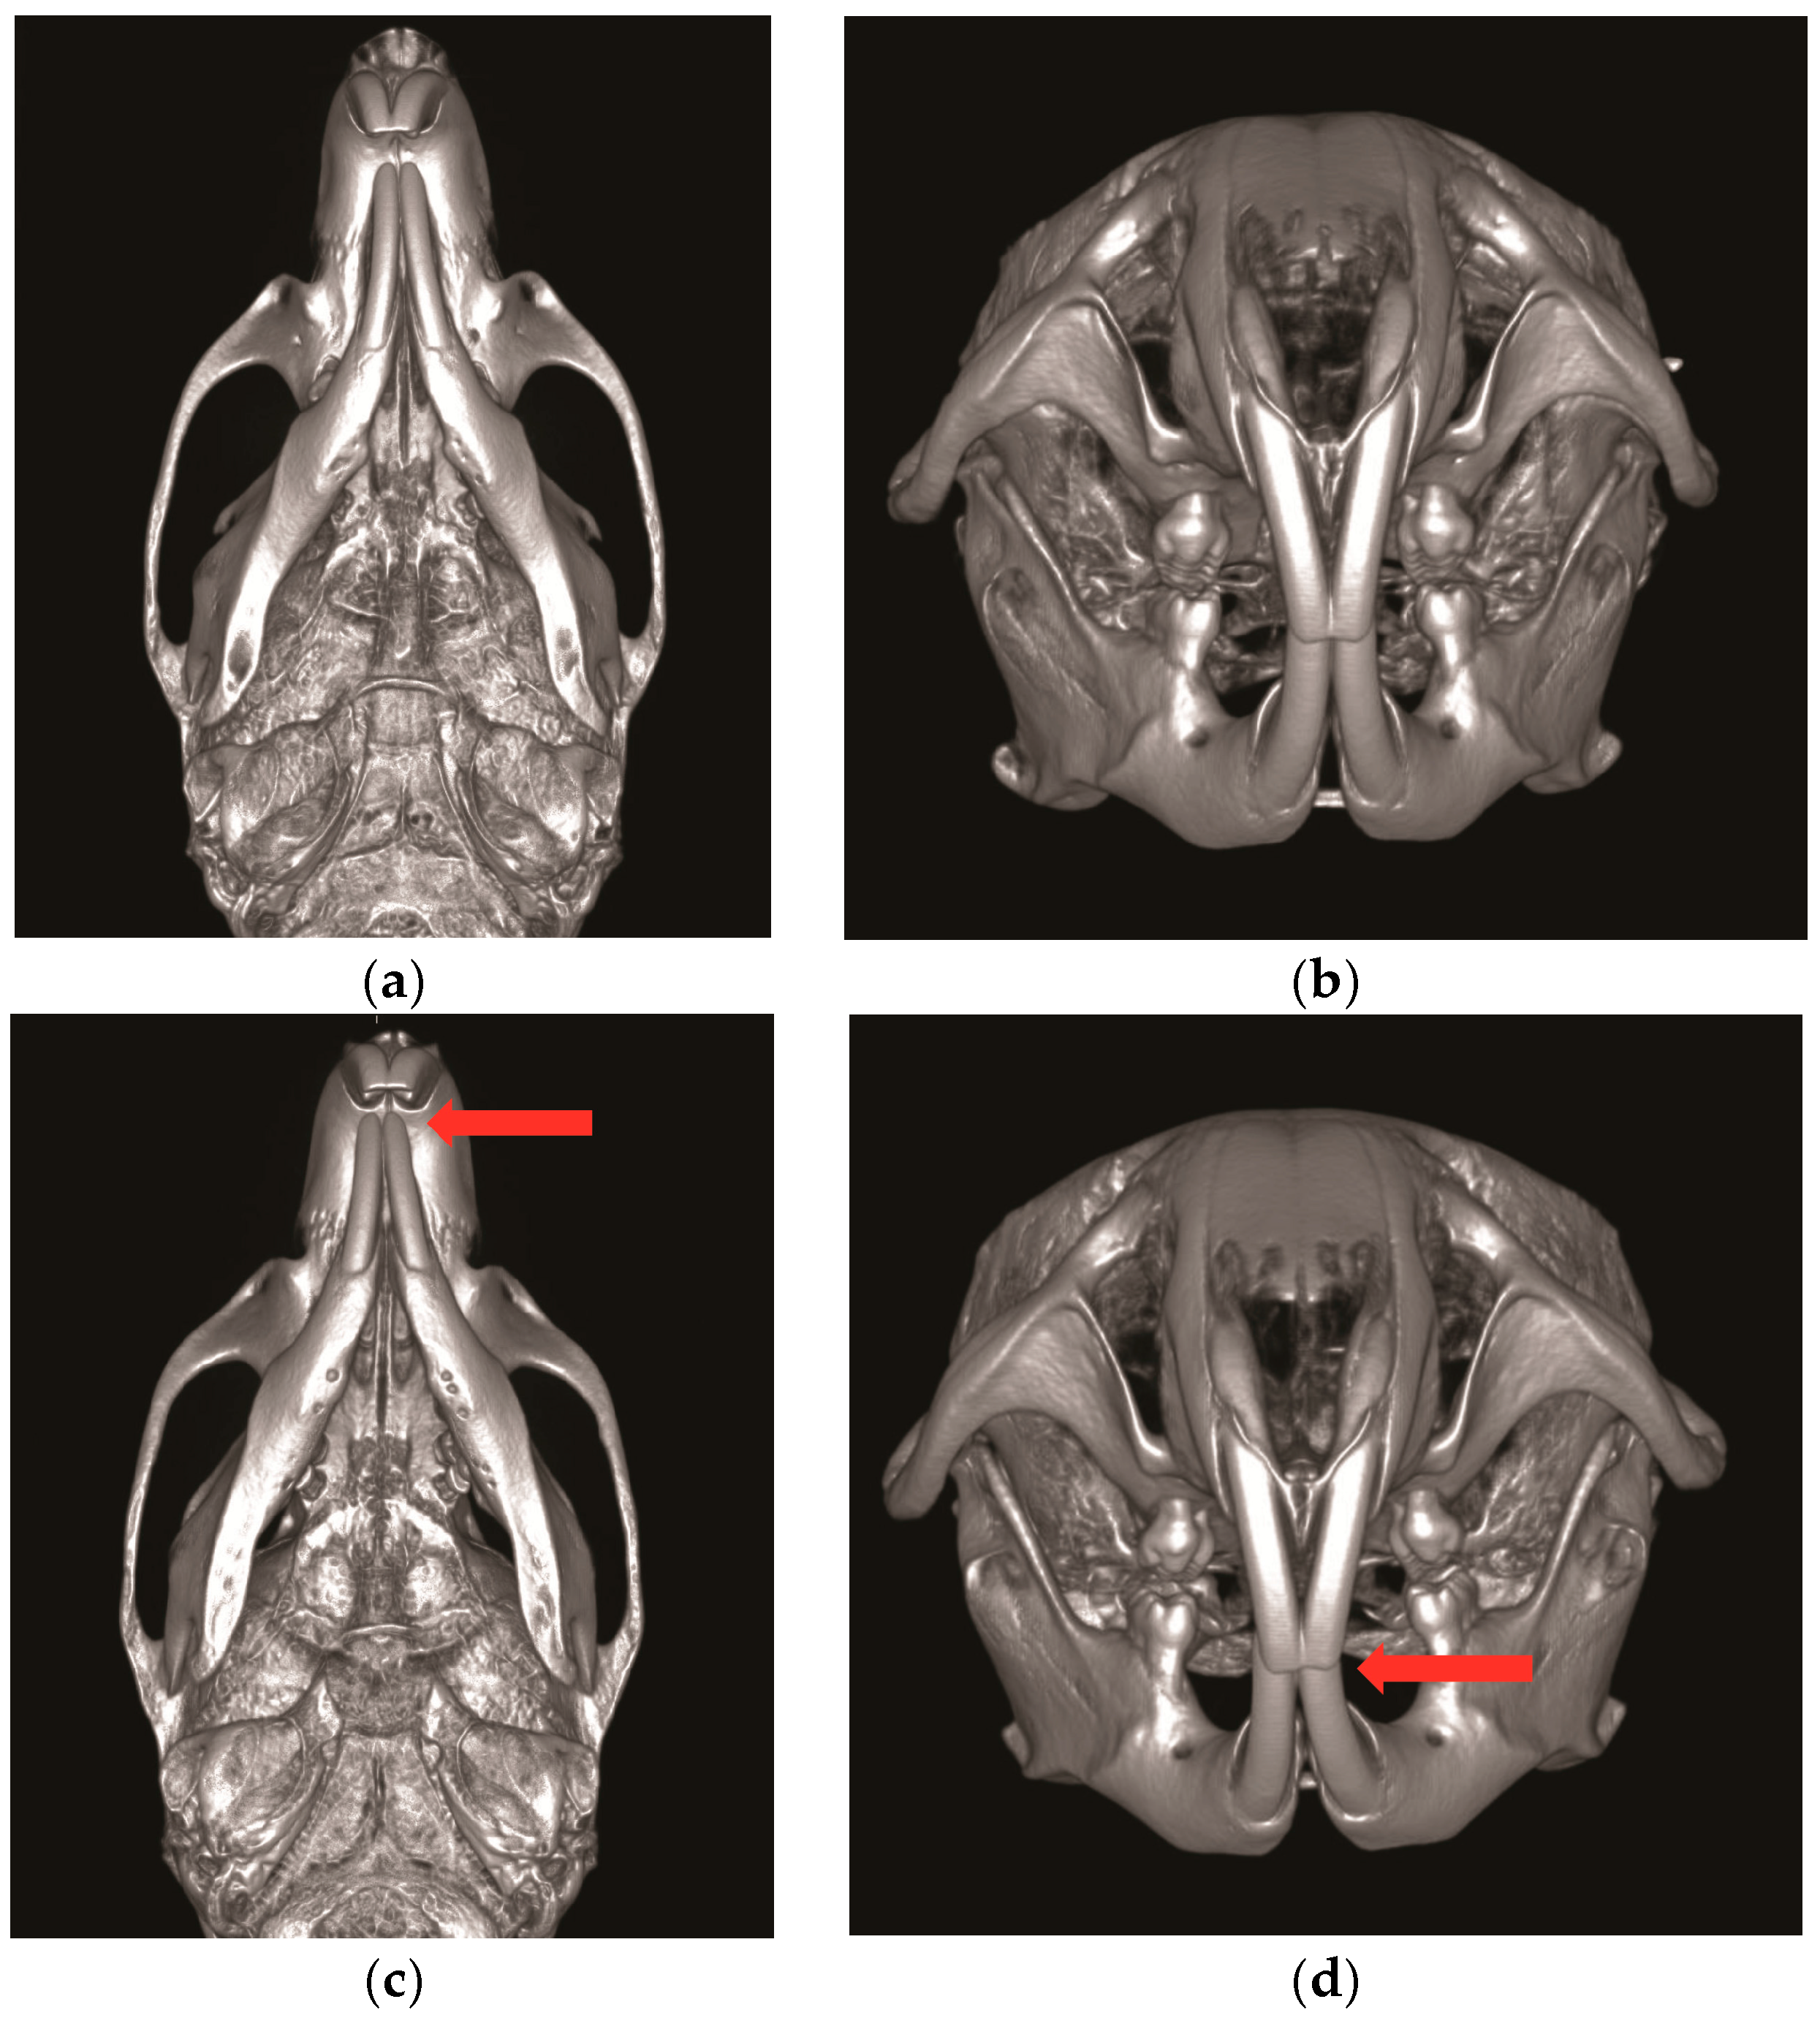

BTX injection in masseter muscles decreases muscle activity and affects the maxillofacial bone growth in animal studies [16,45]. Masseter muscle is attached to the zygomatic arch and inserted to the ramus and angle of mandible [47]. With the use of unilateral BTX injection in rabbit masseter muscle, the bone volumes of zygomatic and mandibular bone are significantly reduced [43]. In addition, with BTX injection in the masseter of growing rat, the mandibular length and ramus height are also significantly reduced (Figure 1 and Figure 2) [17]. The unilateral injection of BTX in masseter muscle induces the growth retardation of mandible (Figure 2) [17,18,48] and causes mandible deviation and facial asymmetry in adult rats (Figure 2c,d) [36]. The BTX injection in temporalis muscle also affects craniofacial bone growth. The temporalis muscle extends from the temporal bone and to the coronoid process of mandible [18]. Rats that received BTX in unilateral temporalis muscles had a significantly reduced skull base dimension [18], and the premaxilla, maxilla, and zygomatic arch dimensions were also decreased [18]. These previous animal studies show that the hypofunction of masticatory muscle by BTX injection affects the growth potential of the involved craniofacial bone and induces morphological changes in facial bone growth [17,43].

Figure 2.

Unilateral Botulinum toxin (BTX) injection to the right masseter muscle induces the retardation of mandible and facial asymmetry. (a,b) The control group with saline injection to the right masseter muscle; (c,d) the experimental group with BTX injection to the right masseter muscle (red arrow; the deviation of the mandible midline to the BTX injection side).